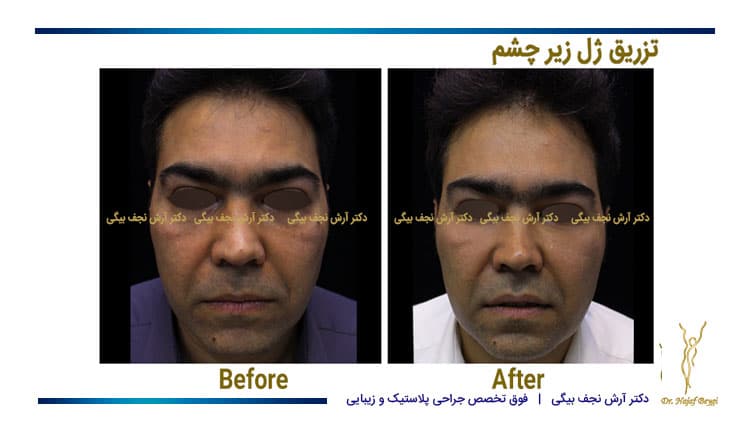

ویدیو تغییر شگفتانگیز: قبل و بعد از تزریق

برای مشاهده نتایج شگفتانگیز تزریق زیر چشم توسط دکتر احمدی، میتوانید ویدیوی قبل و بعد از تزریق را در [لینک ویدیو] مشاهده کنید. در این ویدیو، میتوانید تغییرات چشمگیر در ظاهر بیماران پس از انجام تزریق را مشاهده کنید.

دیدن این تغییرات میتواند به شما در تصمیمگیری بهتر کمک کند و انتظارات واقعبینانهای از نتایج این روش داشته باشید.